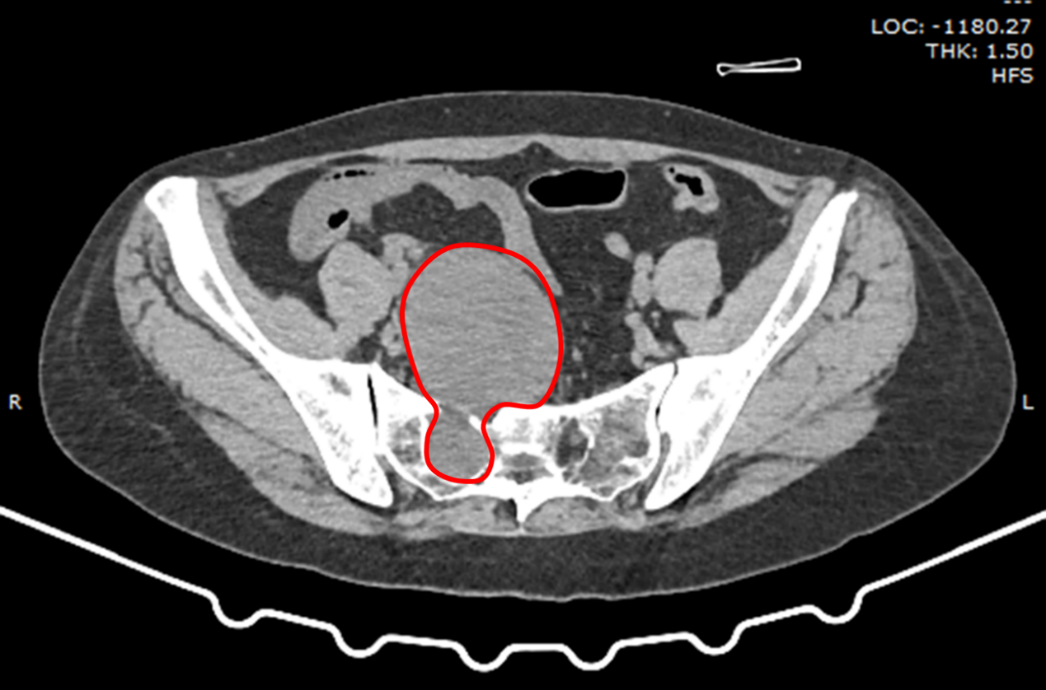

入院后进一步检查发现,郭女士盆腔内的肿瘤确诊为骶骨前神经鞘瘤,大小约8.6*6.5*8cm(前后径*左右径*上下径)。据了解,患者在6年前就发现腹部有一包块,但未引起重视,没有进行治疗,这才引起了更大的健康隐患。

想要拿掉肿瘤可不简单,肿瘤从骶孔穿过,且已经和盆腔内的直肠、子宫争夺“地盘”。巨大的神经鞘瘤将周围的神经紧密包裹,骶孔内的神经也深陷肿瘤内,整个肿瘤更像一个“大葫芦”占据盆腔内,如果任其发展,将会导致严重的后果,必须尽快手术摘除。